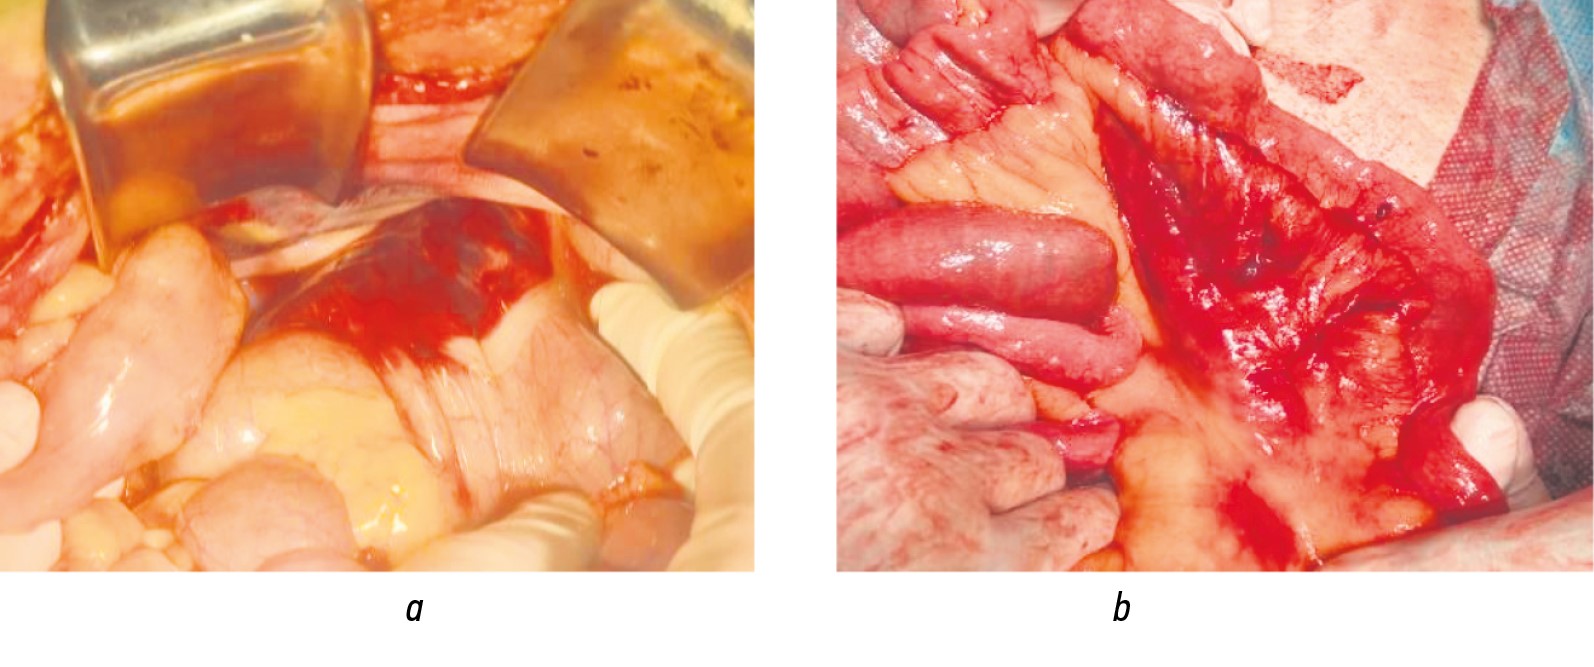

When assessing the role of blast-specific mechanisms of injury formation, signs of brisant action were noted in 24 patients, accounting for 46% of the MG. The direct consequences included traumatic amputations of the upper and lower extremities, which were observed in 14 and 10 cases, respectively (Table 2). In addition, three patients sustained large abdominal wall defects caused by massive tissue destruction following a close-range explosion (Fig. 3).

The most characteristic pathomorphological changes in parenchymal organs under the influence of blast-wave mechanisms were capsule disruptions with formation of subcapsular and intraparenchymal hematomas. In one wounded patient, this resulted in a two-stage splenic rupture with massive hemorrhage (Fig. 4). Among hollow organ injuries of brisant origin, contusion foci in the walls of the small and large intestines and their mesentery predominated, which were accompanied by hematoma formation (Fig. 5).

Fig. 5. Consequences of primary blast factors on hollow organs: a, 34-year-old patient with contusion focus in the wall of the sigmoid colon; b, 37-year-old patient with extensive hematoma of the small bowel mesentery.